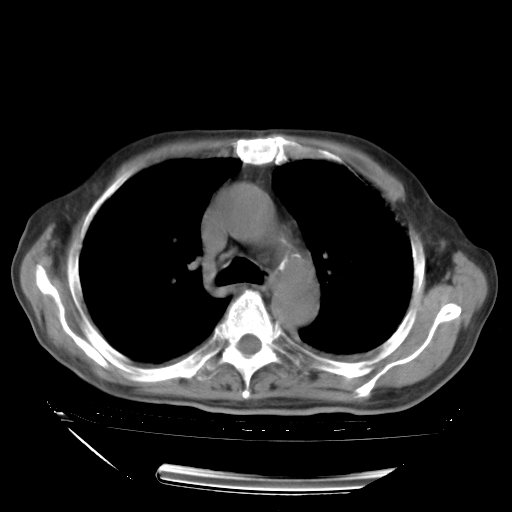

甲强龙80mg/日+抗结核治疗(异烟肼+利福霉素+乙胺丁醇)10天。复查肺部CT。

治疗10天肺部CT